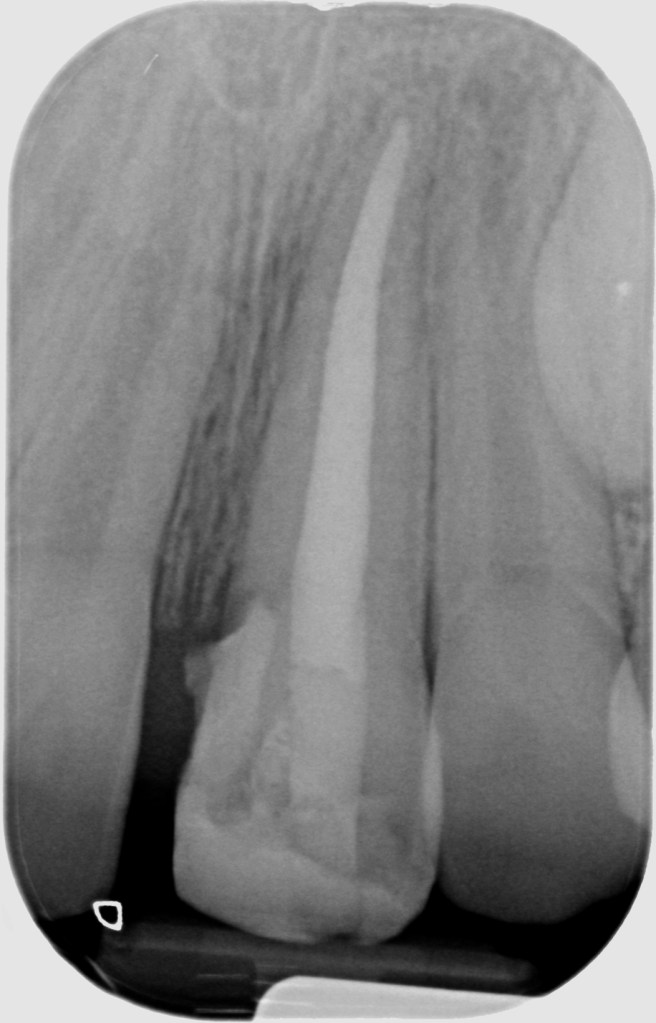

22.10.2021 Patient LM, geb. am 29.02.2008, Zahn 21, WF- Kontrolle